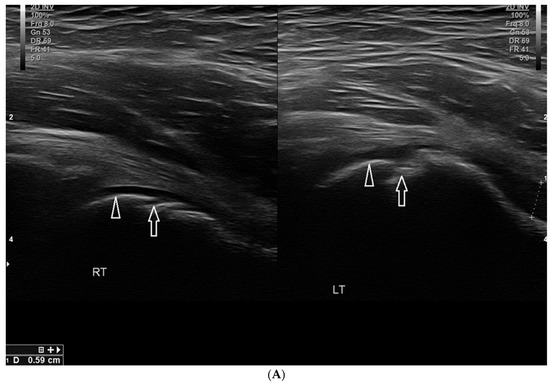

Basic Differences and Most Common Findings in Ultrasound Examinations of Musculoskeletal System in Children: A Narrative Literature Review

by Tomasz Poboży, Wojciech Konarski, Karolina Piotrowska-Lis, Julia Domańska, Kamil Poboży and Maciej Kielar

We present basic differences in the musculoskeletal ultrasound examinations between adults and children. Examiners who deal with adults on a daily basis have shared concerns about examining children. Such concerns may arise from the different approach to child ultrasounds, but they also come [...] Read more.

We present basic differences in the musculoskeletal ultrasound examinations between adults and children. Examiners who deal with adults on a daily basis have shared concerns about examining children. Such concerns may arise from the different approach to child ultrasounds, but they also come from differences in anatomical characteristics according to developmental age. We discuss the presence of growth plates, as well as non-mineralized parts of the bones. We also refer to the pathologies most often found in ultrasounds in early developmental stages. In the PubMed database, the set of keywords: “msk ultrasound in children”, “pediatric msk sonoanatomy”, “coxitis fugax”, “pediatric Baker’s cyst”, “Baker’s cyst ultrasonography”, “bone septic necrosis in ultrasonography”, “ultrasonography in juvenile idiopathic arthritis”, and “ultrasonography in juvenile spondyloarthropathies”, was used to identify a total of 1657 results, from which 54 was selected to be included in the article. We discuss the problem of osteochondritis dissecans, Osgood-Schlatter disease, examples of ligament injuries (especially in relation to the knee and ankle joints), exfoliation of growth cartilages, osteochondroma, exudates and inflammations affecting joints, and Baker’s cysts. In this way, we have collected useful information about the most common diseases of the musculoskeletal system in children. Full article